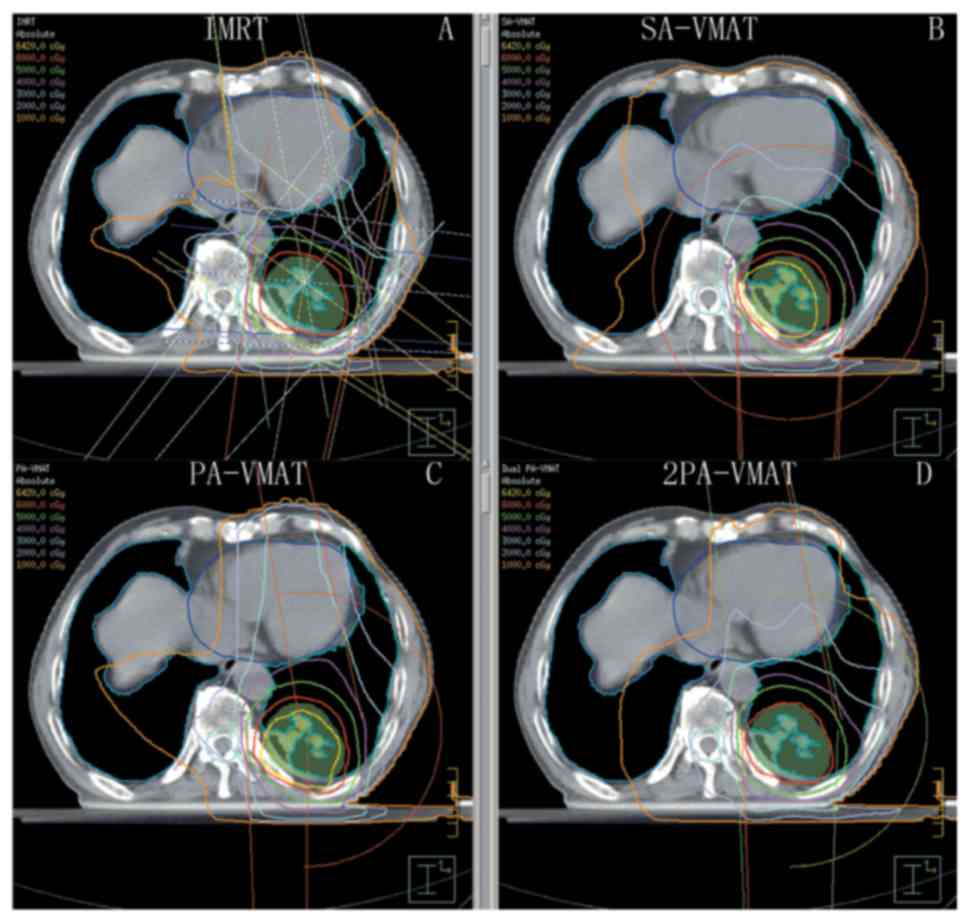

In central lung cancer, in case of either SCLC or positive metastatic mediastinal lymph nodes, PTV needs to encompass the mediastinum. Fig. 7 illustrated the DVH and dose distributions of IMRT and VMAT plans of a patient with central lung cancer whose PTV encompasses the mediastinum. Figs. 8 and 9 illustrate the CI, HI and OAR dosage of each patient.

Figure 7.

Isodose curves of 2PA-VMAT and IMRT plans in central lung cancer in which the target volume encompasses the mediastinal lymphatic drainage region. (A) Isodose curves of IMRT plan. (B) Isodose curves of SA-VMAT plan. (C) Isodose curves of PA-VMAT plan. (D) Isodose curves of 2PA-VMAT plan. In central lung cancer, when PTV encompasses the mediastinum, 2PA-VMAT exhibited improved PTV coverage compared with IMRT. IMRT exhibited better sparing of spinal cord, lung-all, lung-ipsilateral, and lung-contralateral compared with 2PA-VMAT. In addition, IMRT exhibited better dose conformity and homogeneity. 2PA, double partial arc; VMAT, volumetric modulated arc therapy; IMRT, intensity-modulated radiation therapy; PA, partial arc; SA, single arc; PTV, planning target volume.

In the case of PTV encompassing the mediastinum in central lung cancer, Table IV illustrated the dosage comparison between VMAT and IMRT plans. 2PA-VMAT exhibited superior HI and CI compared with IMRT, SA- and PA-VMAT in most cases, but V40 (%) of heart in 2PA-VMAT was higher compared with IMRT, SA- and PA-VMAT. V5, V30 (%) of lung-all in 2PA-VMAT was higher compared with IMRT. By contrast, V20 (%) of lung-all in 2PA-VMAT was less compared with IMRT, SA-, and PA-VMAT. V5, V10 (%) of lung-contralateral in SA-, PA-, and 2PA-VMAT was higher compared with IMRT, while V20, V30 (%) of lung-contralateral in 2PA-VMAT was less compared with IMRT.